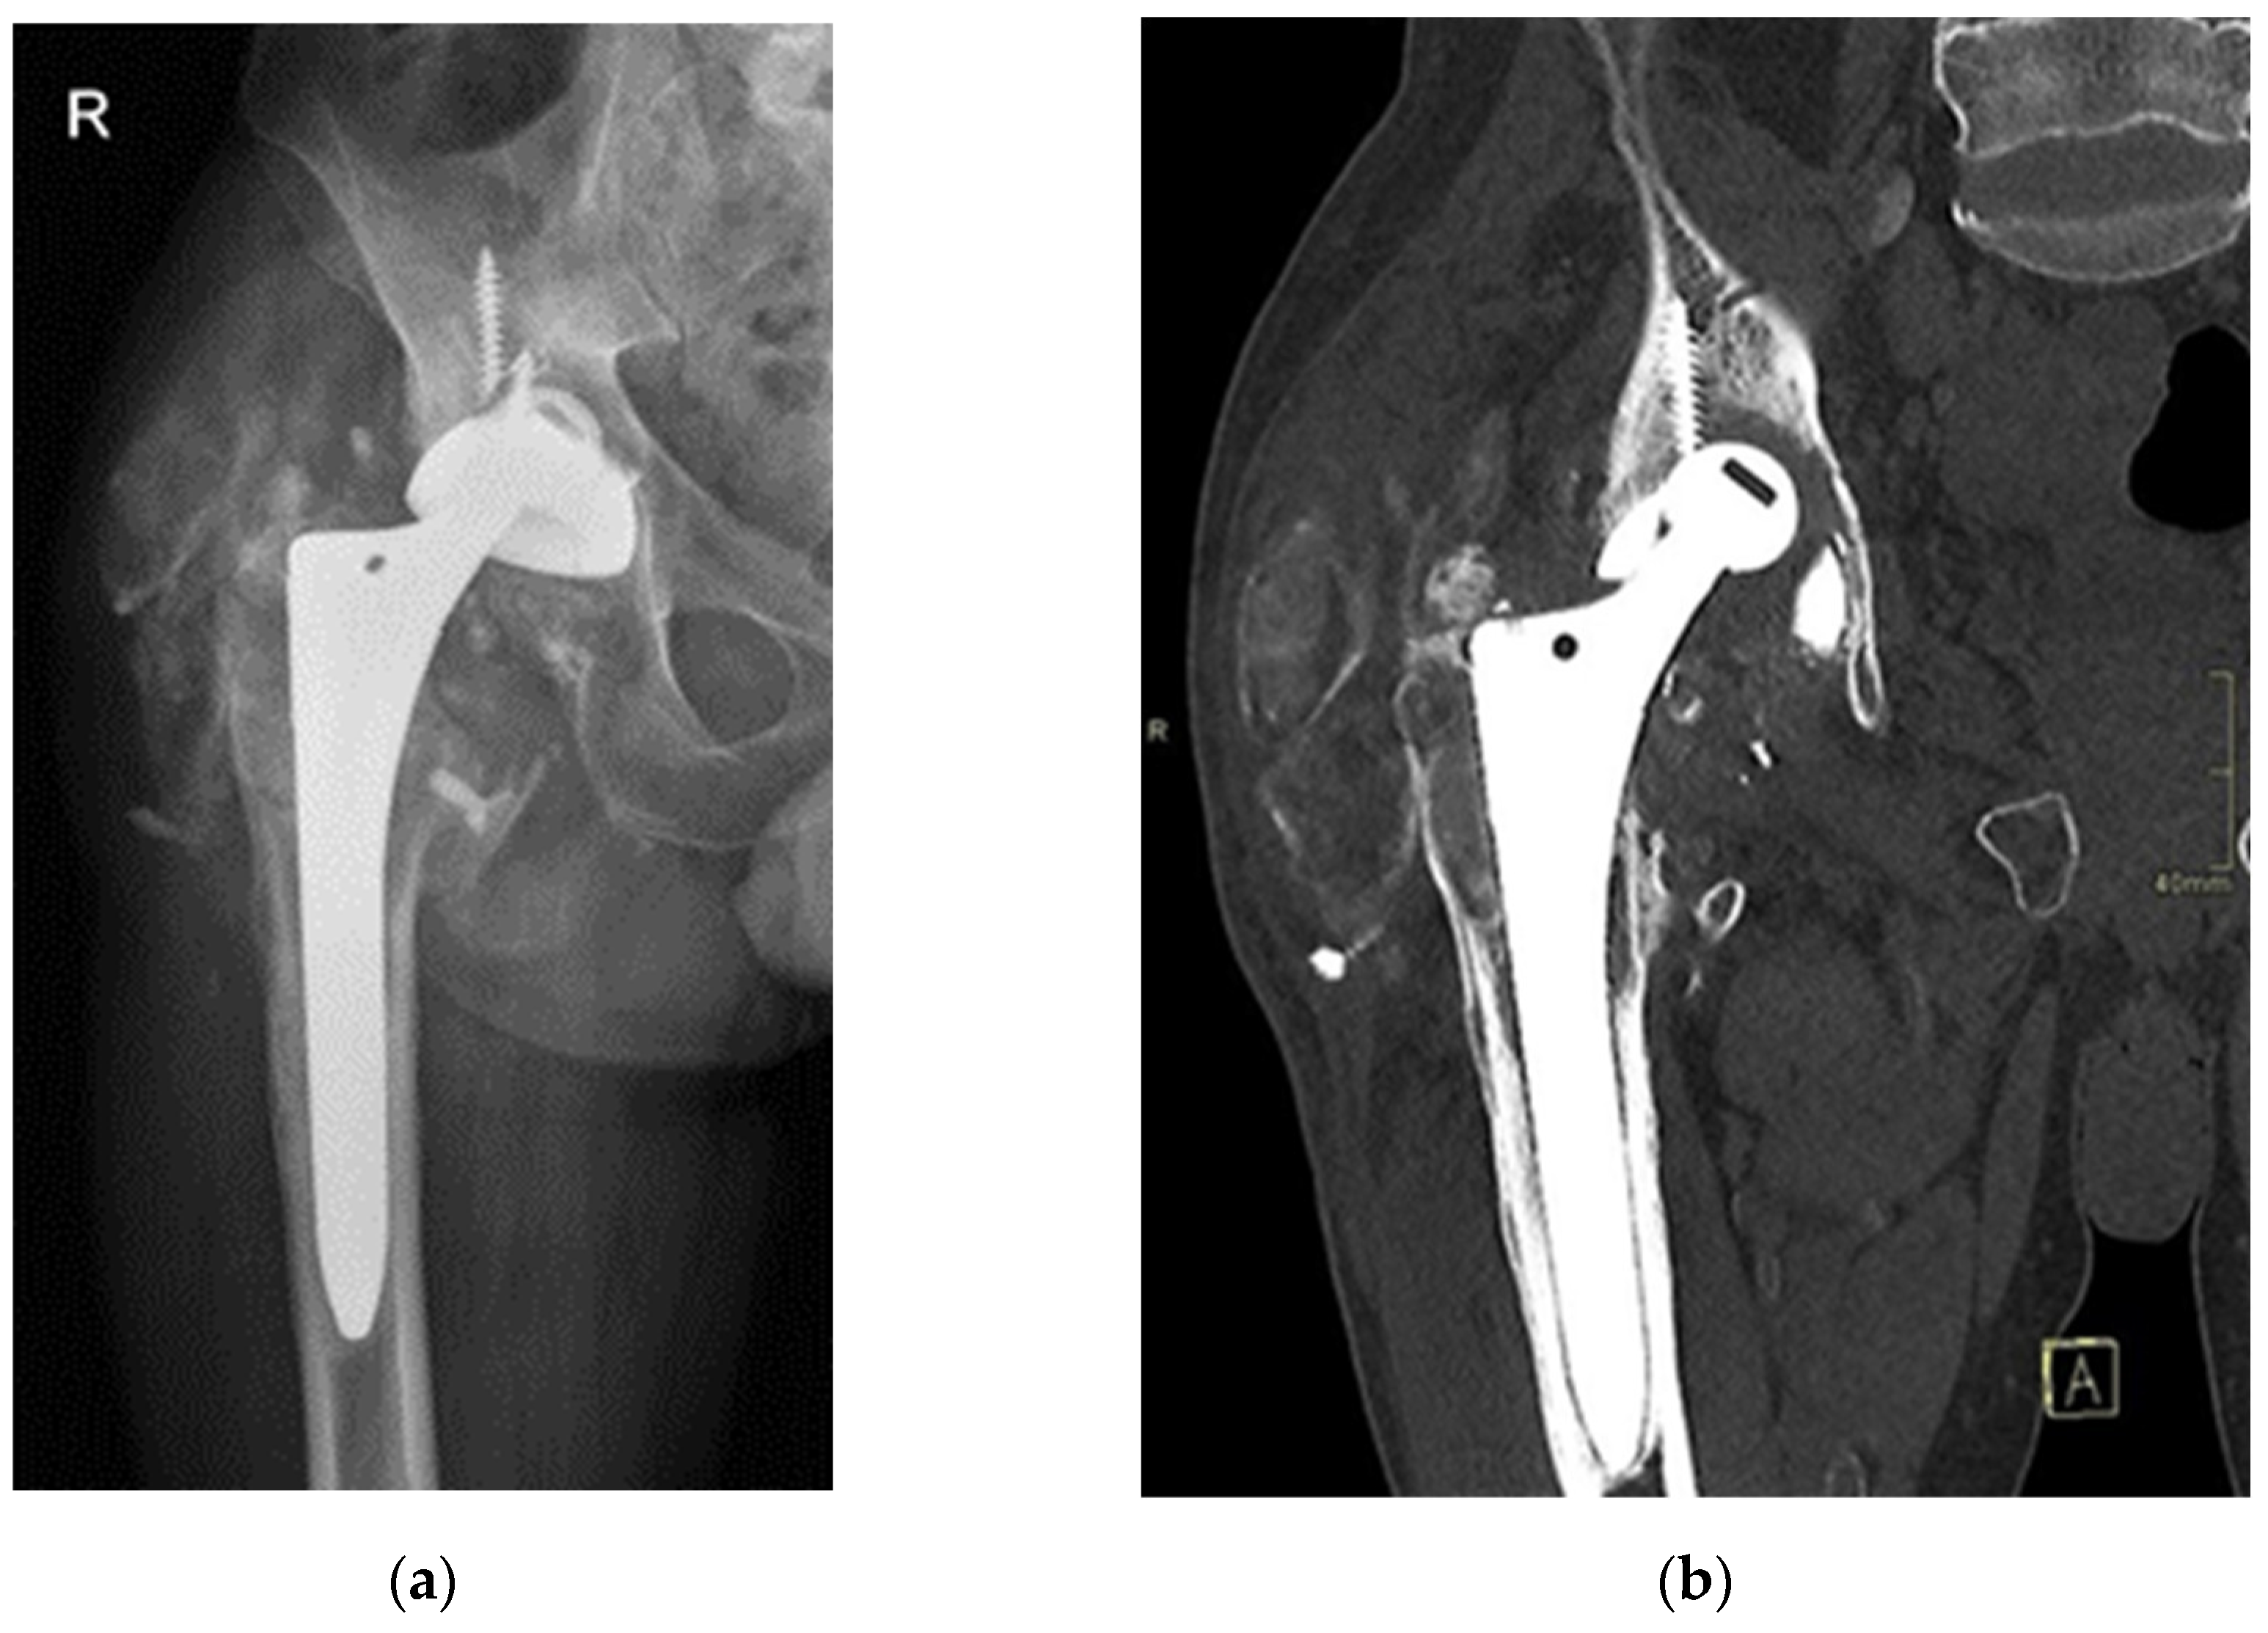

Despite the absence of pain, the patient reported unusual sounds in the hip during weight-bearing, linked to the ceramic-on-ceramic (CoC) bearing. Standard radiographs of the right hip were deemed normal, as depicted in the first available postoperative X-ray (Figure 1). Therefore, no further evaluation or specific treatment was advised for the patient.

Seventeen years post-THA, the now 52-year-old patient presented to our outpatient clinics with groin pain and severely limited range of motion. The patient’s Harris Hip Score (HHS) was 48 points. Laboratory parameters, including white cell count, haemoglobin level, liver and kidney function, erythrocyte sedimentation rate (ESR), and C-reactive protein (CRP) level, were within normal limits. Separate blood samples were taken and stored in special containers (BD Vacutainer® Trace Element, Becton Dickinson, Franklin Lakes, NJ, USA). Serum levels of titanium, aluminium, and vanadium were determined at the nationally accredited laboratory (Clinical Institute for Clinical Chemistry and Biochemistry, Ljubljana, Slovenia) for trace element analysis. X-rays and computer tomography (CT) evaluation revealed protrusion of the alumina ceramic head through the Ti6Al4V acetabular cup (Figure 2), prompting scheduling for an early THA revision.

Figure 2. Radiographic imaging of the patient’s right hip 17-years after primary THA. Note alumina ceramic femoral head protrusion through the acetabular cup, extensive calcifications in the soft tissues and osteolysis. (a) Antero-posterior X-ray; (b) Computer tomography (CT) scan with coronal reconstruction.